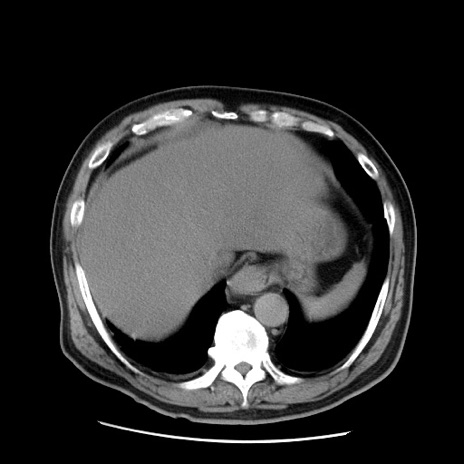

症例20(横断像)

【症例】 60歳代男性

【主訴】 腹部膨満、嘔吐

【現病歴】5日前頃より倦怠感を認め食事量減少し4日前の朝嘔吐、食事摂取困難となった。 3日前近医受診し点滴施行され整腸剤などを処方された。 当日他院を受診し、腹部膨満著明、炎症反応の上昇(CRP10.8、WBC11200)あり、紹介受診となる。

【身体所見】 意識JCS1 受け答えがはっきりしないBP 111/57mHg、 P 67bpm、、BT35.2°C、SpO2 97%(RA)、 腹部:膨隆、打診で鼓音あり、全体的に圧痛有り、腸蠕動音(-)、反跳痛ははっきりせず。

【データ】WBC 11400、CRP 14.20